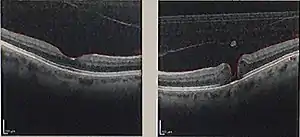

| Optical coherence tomography (OCT) of a macular hole (right) as compared to a normal macula. | |